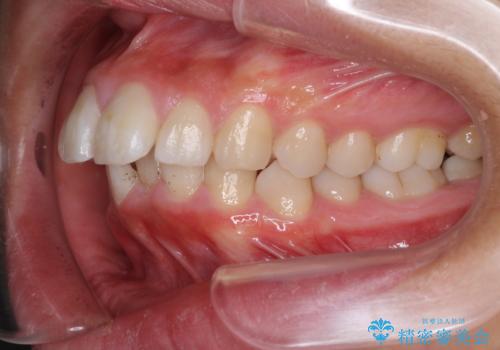

途中で来院されない時期があったため、期間が長引き、更には磨き残しが多かったことで虫歯が多く発現してしまいました。

しっかりと通院するようになってからは順調に治療が進み、横顔の印象が変わるほどスッキリとした口元となりました。